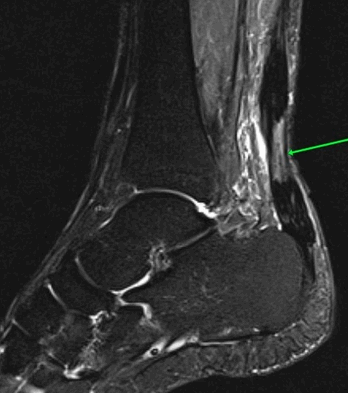

На Т2-ВИ в сагиттальной и корональной плоскостях определяется стресс-перелом дистальных отделов малоберцовой кости.

На Т2-fs-ВИ в сагиттальной плоскости определяется разрыва пяточного сухожилия.